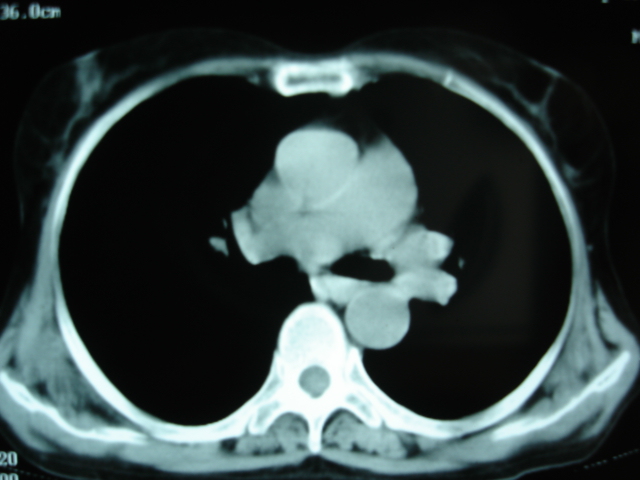

以下是引用卜一在2009-9-7 19:51:00的发言:[br][br] 1 左侧胸内甲状腺占位-多考虑甲状腺腺瘤! 2、左肺门占位-建议增强扫描以便明确性质。 3 慢支并感染! [br]

以下是引用shibing在2009-9-7 20:40:00的发言:[br]左侧胸内甲状腺占位-多考虑甲状腺腺瘤! 2、左肺门占位-建议增强扫描以便明确性质。 3 慢支并感染! [br]